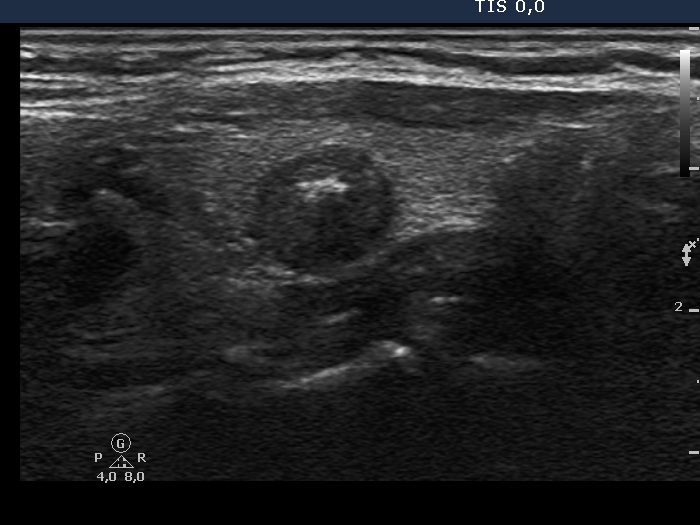

Ultrasonography. The thyroid was echonormal and contained two lesions, one in the right and another one in the left lobe. Both nodules were hypoechogenic and presented microcalcifications. The vascularization was decreased. There was an enlarged lymph node in the left submandibular area of the neck.

The primary tumor in the right lobe has lobulated or spiculated margins, while the metastatic lymph node does lobulated margins.